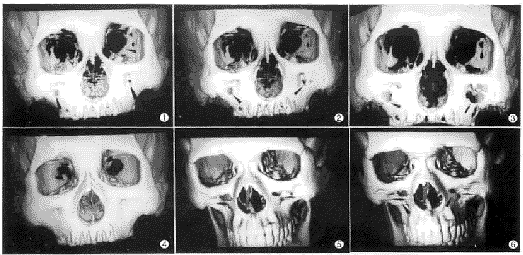

图1 干颅骨SSD,床速3mm,层厚3mm,2mm间隔重建,阈值150。▲所示为上颌窦前壁“假孔”及眶内“假孔” 图2 干颅骨SSD,床速5mm,层厚3mm,2mm间隔重建,阈值150。上颌窦前壁“假孔”及眶内“假孔”和图1比较略有增大 图3 干颅骨SSD,床速5mm,层厚5mm,2mm间隔重建,阈值150。上颌窦前壁“假孔”及眶内“假孔”和图2比较有明显增大 图4 干颅骨SSD,床速5mm,层厚3mm,2mm间隔重建,阈值-500。上颌窦前壁无“假孔”;眶内“假孔”较图2明显减小 图5 志愿者颌面SSD,床速5mm,层厚3mm,2mm间隔重建,阈值150。▲所示为上颌窦前壁“假孔” 图6 志愿者颌面SSD,床速5mm,层厚3mm,1mm间隔重建,阈值150。上颌窦前壁“假孔”与图5比较略有变小。但可见和扫描平面平行的条状影 图7 干颅骨实物